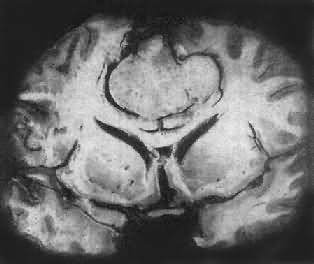

肉眼观,肿瘤为数厘米的结节至巨大块状。分化较好的肿瘤,境界不清;而分化程度较低的肿瘤则境界分明。瘤体灰白色。质地视肿瘤内胶质纤维多少而异,或硬、或软、或呈胶冻状外观,并可形成大小不等的囊腔。由于肿瘤的生长、占位和邻近脑细胞的肿胀,脑的原有结构因受挤压而扭曲变形(图16-23)。

图16-23 星形胶质细胞瘤

左大脑半球肿胀,肿瘤边界不清,部分呈胶冻状

高度恶性的星形胶质细胞瘤称为多形性胶质母细胞瘤(glioblastoma multiforme),多见于成人。肿瘤好发于额叶、颞叶白质,浸润范围广,常可穿过胼胝体到对侧,呈蝴蝶状生长(图16-24)。瘤体因常有出血坏死而呈红褐色。镜下,细胞密集,异型性明显,可见怪异的单核或多核瘤巨细胞。出血坏死明显,是其区别于间变性星形胶质细胞瘤的特征。毛细血管明显增生,内皮细胞增生、肿大,可导致管腔闭塞和血栓形成。肿瘤发展迅速,预后极差,患者多在2年内死亡。

图16-24 多形性胶质母细胞瘤

在两半球内肿瘤呈蝴蝶状,边界不清,切面见有出血、坏死及液化